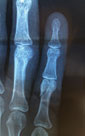

Suggest X-ray, U/S

Choosing the right Hand Therapist starts with them being able to assess your injury, read your X-rays or Ultrasound and then educate and/or fabricate the right brace for you and your injury. The Hand Therapists, Physiotherapists and Occupational Therapists at Action Rehab are experienced in assessing Jersey Finger and other tendon injuries, reading X-rays, reading Ultrasounds and advising on the most appropriate treatment.